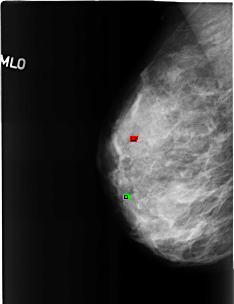

B_3191_1.RIGHT_CC

RIGHT_CC LINES 4584 PIXELS_PER_LINE 3056 BITS_PER_PIXEL 12 RESOLUTION 50 OVERLAY

FILE: B_3191_1.RIGHT_CC.OVERLAY

TOTAL_ABNORMALITIES 2

ABNORMALITY 1

LESION_TYPE CALCIFICATION TYPE ROUND_AND_REGULAR DISTRIBUTION N/A

ASSESSMENT 2

SUBTLETY 5

PATHOLOGY BENIGN_WITHOUT_CALLBACK

TOTAL_OUTLINES 1

BOUNDARY

ABNORMALITY 2